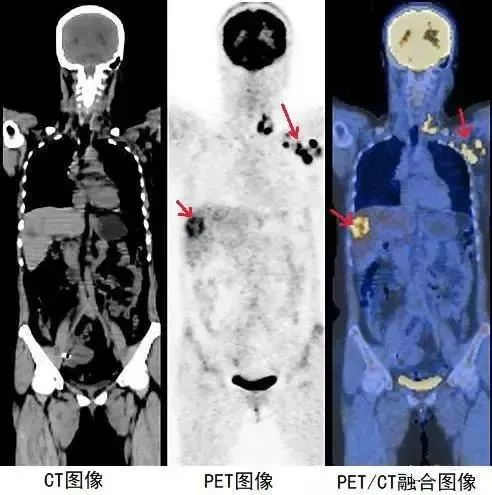

CT与PET的有机结合可将解剖结构影像与功能、代谢、生化影像精确重叠显示,使医生获得最为全面的信息。

这对疾病的诊断,尤其是对肿瘤的诊断、定位和治疗计划有很大帮助。总而言之,CT与PET的结合PET/CT,是一个1+1大于2的技术整合

其融合图像对疾病的早期诊断、病灶定性、手术和放射计划治疗定位、小病变的诊断与鉴别、以及一些目前尚不清楚的代谢疾病研究和受体疾病研究具有重要价值,是目前核医学影像学的最新发展方向。